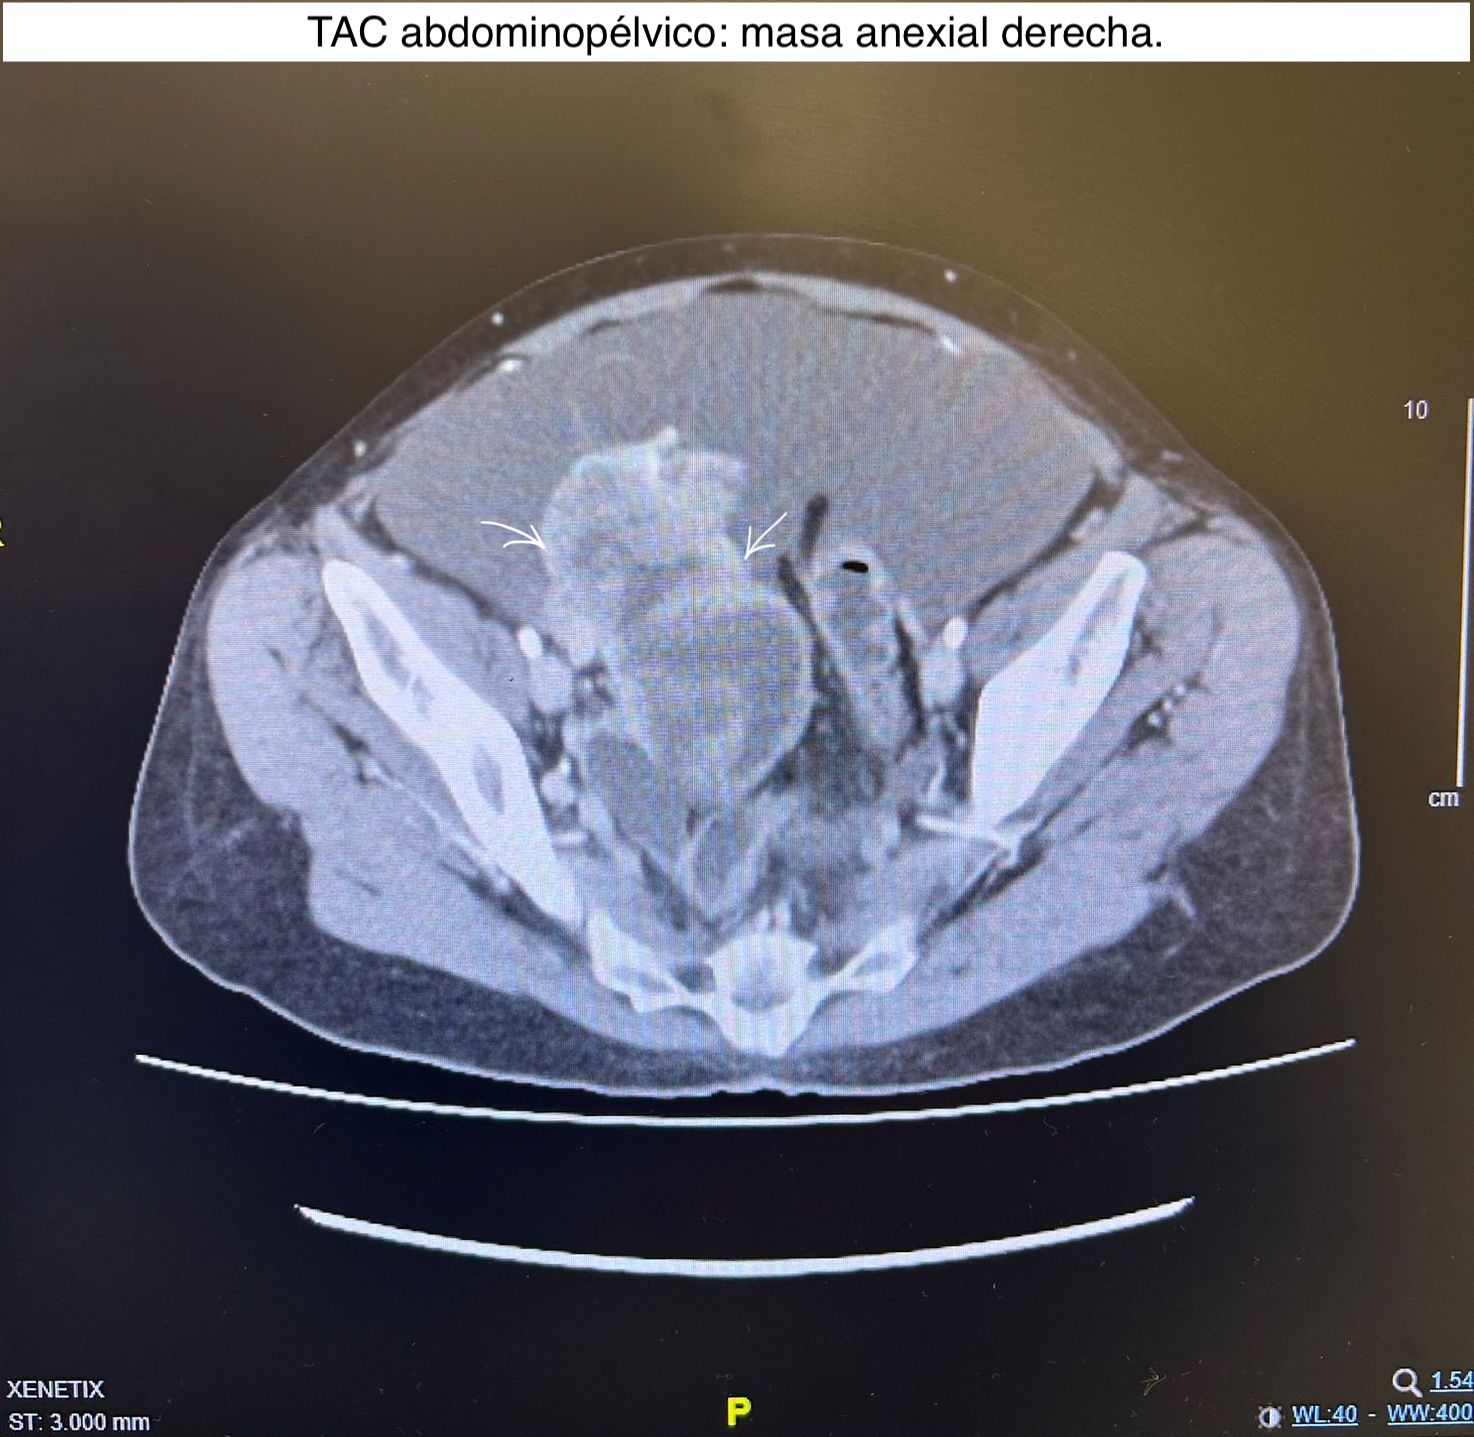

Para evaluar la propagación de la patología se solicita TAC abdomino-pélvico con contraste confirmando el hallazgo de lesión de probable origen anexial derecho con infiltración del mesenterio del íleon y del ligamento redondo hepático, carcinomatosis peritoneal, ascitis, lesiones omentales y capsulares hepáticas.